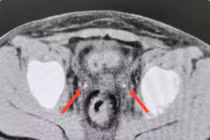

Bệnh nhân được chẩn đoán sỏi niệu quản phải đoạn 1/3 trên, hẹp niệu quản phải kèm nhiễm trùng đường tiết niệu – một tình trạng bệnh lý có thể gây đau đớn kéo dài, ảnh hưởng lớn đến sức khỏe và chức năng thận nếu không được điều trị kịp thời.

Theo các bác sĩ, bệnh nhân nhập viện với biểu hiện đau âm ỉ vùng hông lưng phải kéo dài, tiểu buốt, tiểu rắt, kèm dấu hiệu nhiễm trùng. Kết quả thăm khám cho thấy viên sỏi nằm ở vị trí cao của niệu quản gây cản trở dòng chảy nước tiểu, trong khi đoạn niệu quản bị hẹp khiến tình trạng ứ đọng trở nên nghiêm trọng hơn, làm tăng nguy cơ nhiễm trùng lan rộng và suy giảm chức năng thận.